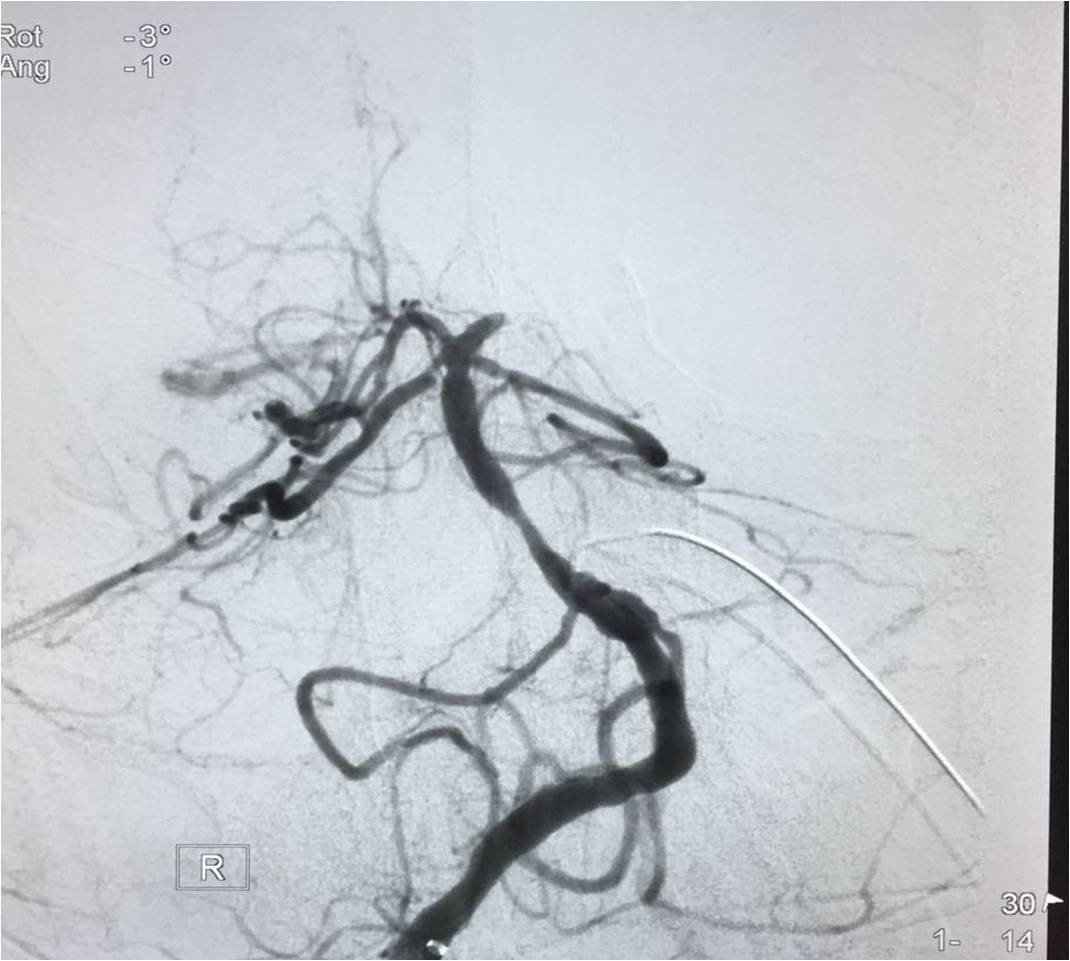

▼将Solitaire FR 送进微导管后将支架至于闭塞。部位远端,定位释放支架,保持原位5-10分钟后,将支架和微导管同时回撤。